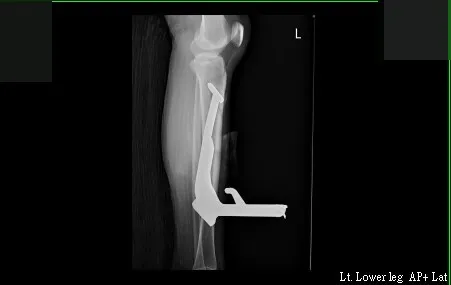

在X光片影像中,可看到長達23公分的中柱,直直插在李小姐左腿裡。讀者提供